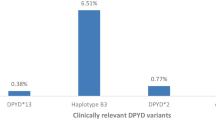

Surprisingly, DPD deficiency was evidenced in about 40% of the patients included in this study, an observation by far higher than the score usually expected with DPYD genetic polymorphism [30] but consistent with other recent clinical reports [36]. This higher figure can come from the strategy we used to evaluate DPD status. Here, DPD issue was addressed primarily following a functional testing, and not some kind of genetic studies that proved over the past to generate false-negative results [15]. However, intriguingly, the present figures were still much higher than the frequency of deficient patients we previously observed in another study using the same phenotypic method, in which about 10–15% of the patients displayed DPD deficiency [6]. This discrepancy could come from the medical history of the patients we included. Patients with HNC frequently have a record of tobacco-alcohol history, and little is known on the impact these characteristics might have on DPD functionality in the liver. Similarly, pancreatitis and hepatitis along with other hepatic disorders frequently observed in this very population could have impacted as well on the DPD status. Further experiments will have to be conducted to elucidate whether alcohol-tobacco dependence can lead to DPD dysfunction, as it does for other liver enzymes such as cytochromes P450 [22]. Additionally, patients with HNC are more frequently co-administered than other patients with a variety of drugs for supportive care (e.g., local antibiotics and artificial nutrition) likely to interact with DPD activity, on a classical drug–drug interaction basis.